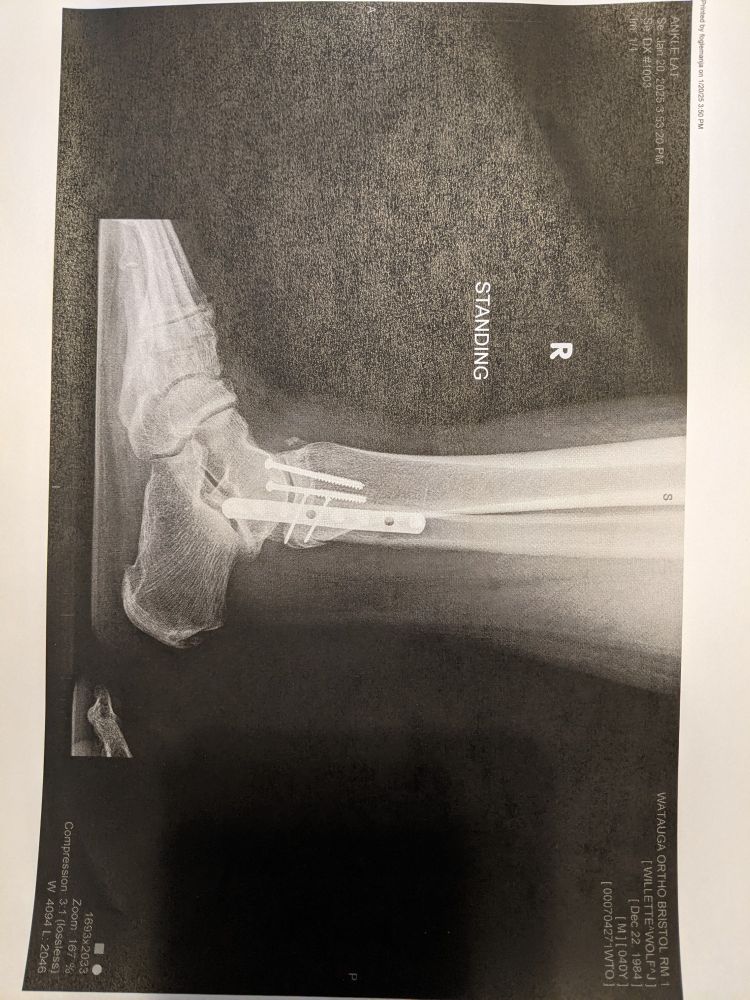

End of September I broke my leg in 3 places and dislocated my ankle.

I misstepped the 2nd to last step going down the stairs and I was on the phones and websites etc off and on since then for all the issues and efforts to get things taken care of. Red tape and back n forths that I'm sure are less hassle than most face. But it's a lot, physical therapy was done solo.

Struggling to make ends meet while simultaneously trying to rebuild my leg and body strength and endurance is oof.

I'm not as present online and with the roll outs of all the other stuff, I'm just trying to get myself back to work safely and take care of my family adjusting to my limitations. Art will hopefully pick up again in the mix too.